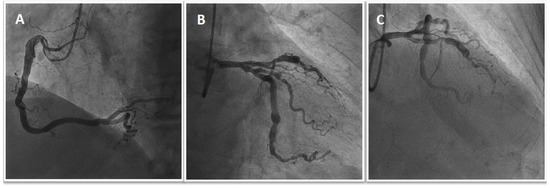

1.2. Patient 2

1.3. Patient 3